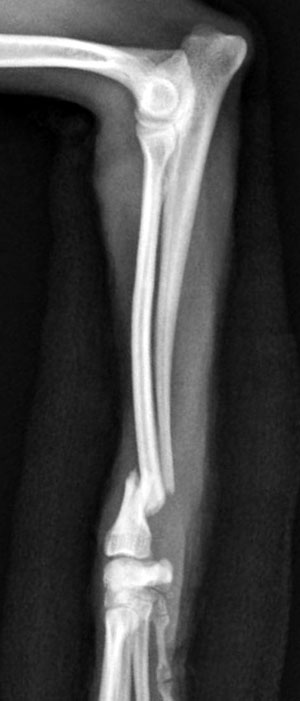

左前腕骨折のトイプードルちゃんの手術がありました。橈尺骨骨折は動物病院では一番よくある骨折です。ロッキングプレートであるTAITANコンディラー1.7mmで対応しました。治りも順調で元気に帰りました。よかったね。